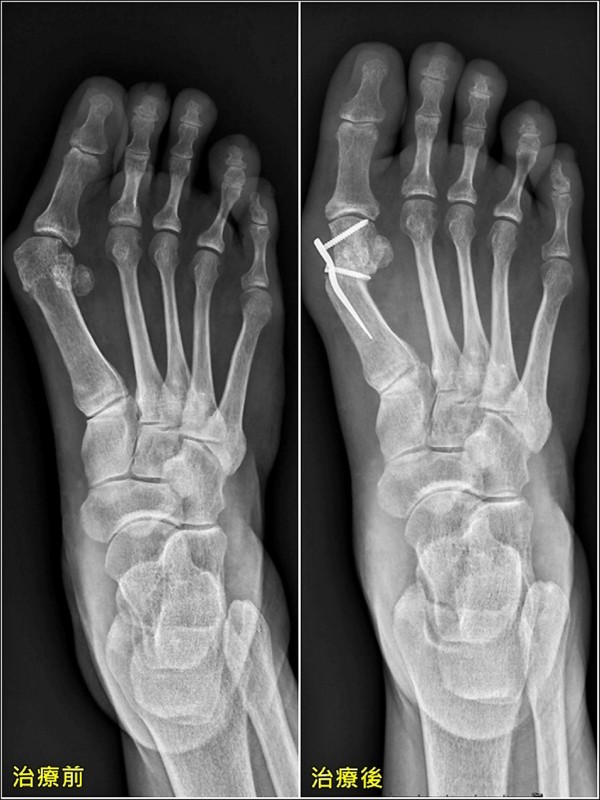

▲X光影像。(照片提供/王大翊)

▎外翻超過40度 保守治療無效

透過檢查發現,許女士拇趾外翻超過40度,且透過保守治療無法減緩症狀,故透過拇趾外翻矯正手術治療,透過修補軟組織,以及切骨矯正,放鬆拇趾外翻緊繃的韌帶,拉緊內側鬆弛的韌帶,並將往內轉移的大拇趾矯正到理想的角度,術後需練習腳趾抓握訓練、穿鞋墊,才能讓腳維持在正位上,避免病情復發。